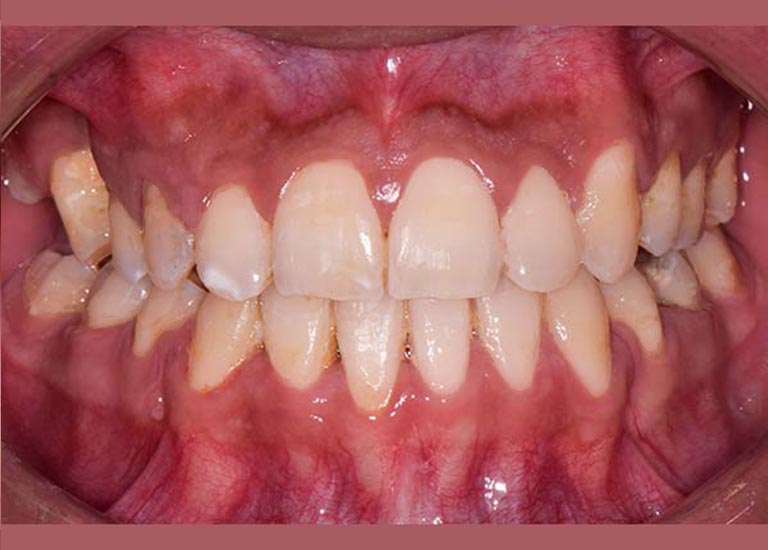

BEFORE

My young friend visited me suffering from a complete Bite collapse, a severe anterior crossbite, in addition to the loss of many of his back teeth. He was so frustrated, thinking that his case is incurable, and this frustration was reflected on his shy smile.